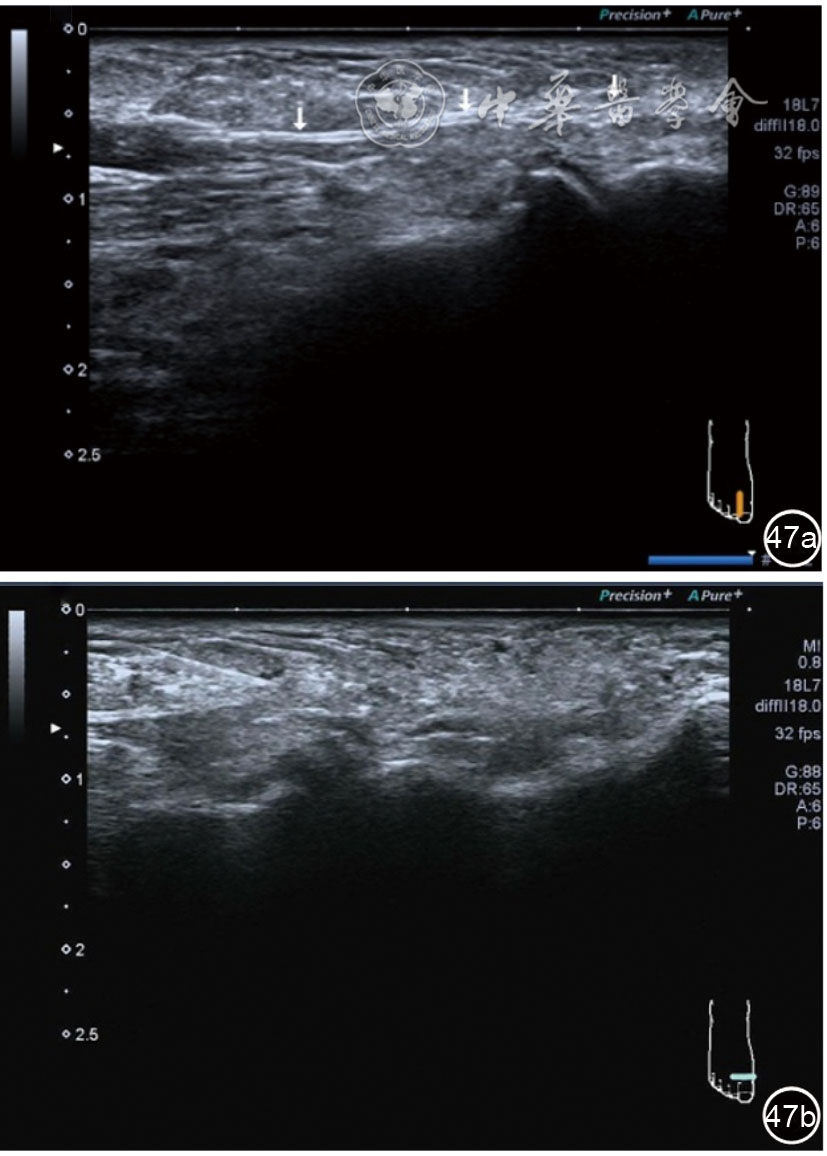

1.关节内表现。(1)骨改变。表现为骨末端或关节周缘出现的骨质局部突起改变,其后方伴或不伴有声影,多见于膝关节内侧缘和外侧缘(图1)。(2)软骨改变。股骨关节面改变可以在长轴及短轴切面显示,嘱患者屈曲膝关节,足平置于检查床,股骨滑车及股骨髁上半部分的关节面即可轻松显示。超声探查可见股骨负重面关节软骨发生不同程度的改变,轻者关节软骨浅侧边界模糊,重者可见关节软骨薄、缺失,软骨下骨缺损改变(图2)。(3)半月板外突。一般内侧半月板突出多见,外侧半月板突出比较少。半月板可见不同程度的外突,同时伴有膝内侧副韧带向外移位(图3)。半月板外周缘性滑脱是指半月板突出超出胫骨平台边缘的距离≥3 mm,其可引起一系列临床症状,早期诊断、早期治疗可以预防骨关节的进一步损伤。(4)交叉韧带损伤。可见前后交叉韧带增粗,回声减低(图4)。(5)髌上囊积液。膝关节是最容易发生积液的关节之一。患者仰卧位,关节积液最常见于膝关节上外侧,因为关节囊向髌股关节上外侧突出。髌上囊积液采用10~18 MHz的高频线阵探头于股四头肌腱纵断面及横断面扫查均可显示,探头频率取决于患者体型。超声可见低回声积液,慢性可伴有丛状滑膜增生(图5)。(6)脂肪垫水肿。脂肪垫在髌骨附着点处回声增强、增厚(图6)。

图3 半月板突出超声图像

3.超声半定量评估。(1)骨赘超声半定量评估:患者仰卧位,膝关节伸直,探头纵切面置于膝关节内侧与外侧,自前向后移动探头以进行全面扫查。测量骨赘的厚度,并进行半定量分析。0级:无骨赘;1级:小骨赘,厚度<2 mm;2级:中等骨赘,厚度2.1~4.0 mm;3级:大骨赘,厚度>4.0 mm。(2)关节软骨超声半定量评估:患者仰卧位,膝关节完全屈曲。探头置于骨上方,检查股骨内侧髁、外侧髁和股骨滑车处关节软骨三个部位,分别进行横切面和纵切面检查,从近侧向远侧做全面扫查。检查时声束要垂直于股骨表面。关节软骨可按病变严重程度分为四级。0级:关节软骨呈均匀的无回声带,其浅侧和深侧边界清晰。1级:关节软骨浅侧边界不清和(或)内部回声增高。2级:①2A级,关节软骨局部变薄,缺损厚度<50%;②2B级,关节软骨局部变薄,缺损厚度>50%,但<100%。3级:关节软骨局部完全消失,伴或不伴有软骨下骨病变。(3)半月板突出分度:半月板外周缘与胫骨平台边缘之间的距离≥3 mm的突出视为病理变化,诊断为半月板周缘滑脱。按照突出程度分为三度:Ⅰ度,半月板外周缘与胫骨平台边缘之间的距离3~5 mm;Ⅱ度,半月板外周缘与胫骨平台边缘之间的距离>5~8 mm;Ⅲ度,半月板外周缘与胫骨平台边缘之间的距离8 mm以上。